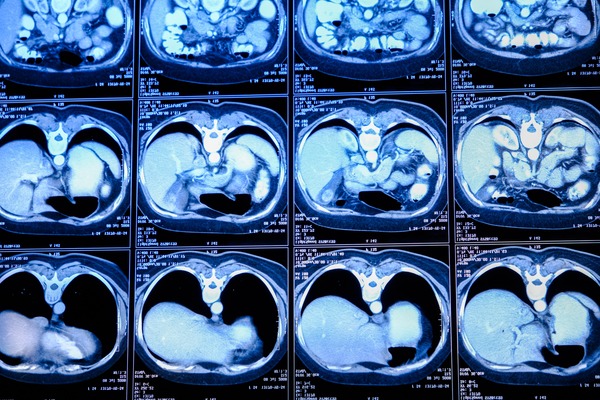

КТ ангиография брахиоцефальных артерий и грудного отдела аорты — это вид инструментальной диагностики, позволяющий выявлять аномальные состояния самых крупных сосудов организма. С помощью компьютерной томографии можно оценить анатомические структуры, обнаружить окклюзию, новообразования, повреждения стенок и другие патологии. Пройти диагностику вас приглашают врачи ЦЭЛТ — передового медицинского учреждения, где каждый пациент может получить точный диагноз, а при желании — пройти лечение у нас в клинике. Мы назначаем современные препараты и проводим операции различного уровня сложности.

КТ грудного отдела аорты с контрастированием

Аорта — это крупнейший сосуд организма, по которому артериальная кровь через более мелкие артерии доставляется во все органы. Брахиоцефальные артерии отходят от аорты и несут кровь к верхней, части тела: шее, голове, рукам. Ангиография может выполняться как в обзорном режиме, так и с контрастом, для более точной детализации всех, даже мелких, сосудов. Выбор зависит от предварительного диагноза и определяется лечащим врачом.